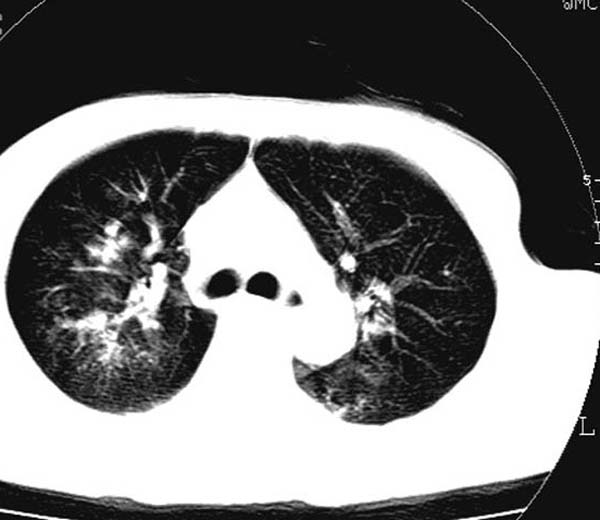

此病人是摔伤后12小时,38岁,无结核病史。谢谢

对不起各位,学着发图片,所以没有发全。此病人是摔伤后12小时,38岁,无结核病史。谢谢!

影像必须密切结合临床!此病例首先考虑肺撕裂伤,间质性改变为主,右侧有创伤性湿肺表现。鉴别诊断诸位大虾已经说得非常ok了。

结合病史,考虑肺挫伤可能,双侧少量胸腔积液.建议短期复查.

肺挫裂伤是肯定有。原来可能有结核或尘肺

影像必须密切结合临床!此病例首先考虑肺撕裂伤,间质性改变为主,右侧有创伤性湿肺表现。鉴别诊断诸位已经说了。

此病例首先考虑肺撕裂伤,间质性改变为主,右侧有创伤性湿肺表现,可短期治疗复查。